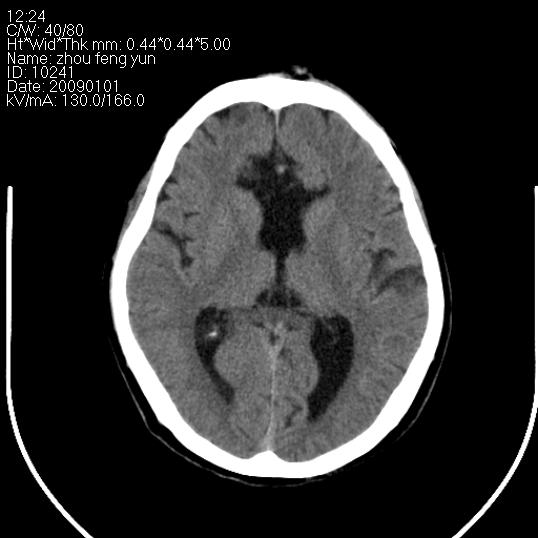

以下是引用hhcckk在2009-1-1 16:39:00的发言:[br]胼胝体嘴、膝部及部分体部发育不全,为囊状影替代,两侧侧脑室分离,脑室后角扩张[br][br]诊断:胼胝体发育不良[br][br]胼胝体发育不良(dysgenesis of the corpus callosum)是最常见的颅脑畸形,是胚胎期背部中线结构发育不良的一种形式。主要包括胼胝体缺如和部分缺如。胼胝体发育不良还可合并其他畸形,如胼胝体脂肪瘤、蛛网膜囊肿、脑膨出、chiari畸形、灰质异位症、脑回畸形等。[br][br]ct诊断要点:[br]1. ct横断扫描可见两侧侧脑室明显分离,脑室后角扩张,形成典型的蝙蝠翼状侧脑室外形。[br]2. 第三脑室扩大并向上插入两侧脑室体部之间,严重者第三脑室可上移到两侧大脑半球纵裂的顶部。在ct冠状扫描位显示更清。[br]4. 胼胝体畸形常伴有脂肪瘤,可测到其特征性脂肪密度。部分脂肪瘤的边缘可出现线样钙化[br]